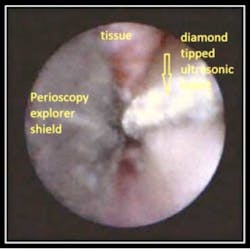

by Dr. John Y. Kwan The below pictures and corresponding video show a tooth with an enamel projection which has developed bone loss. In the video “Enamel Projection,” a Satelec diamond tip was made Magnetostrictive by the Tony Riso Co. and is used to remove the projection and clean into the furcation.

Photo 2 Photo #1 identifies the enamel projection. Photo #2 shows the curved unltrasonic insert removing the projection and cleaning into the furcation.